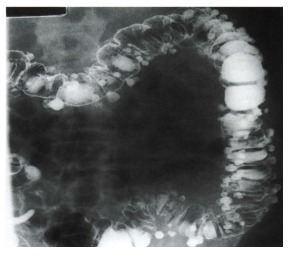

O enema opaco com duplo contraste ilustrado a seguir evidencia uma doença bastante prevalente. A respeito desta doença, assinale a alternativa CORRETA:

Enunciado 3505927-1